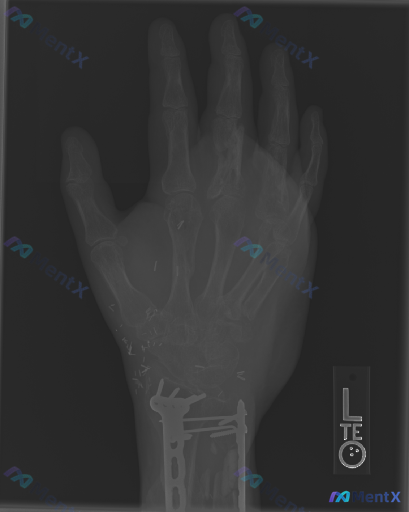

整理到一个左手部的影像病例,资料如下: 背景与影像表现 - 有左腕关节桡骨远端骨折术后史,目前内固定在位,可见骨痂生长 - 左手掌及腕部广泛分布有散在的细小金属高密度影 - 第3掌骨骨干中部至远端骨皮质不连续,骨结构模糊,可见不规则溶骨性改变与骨密度增高混杂表现,骨干呈膨胀性改变,边界不清,第3掌指...